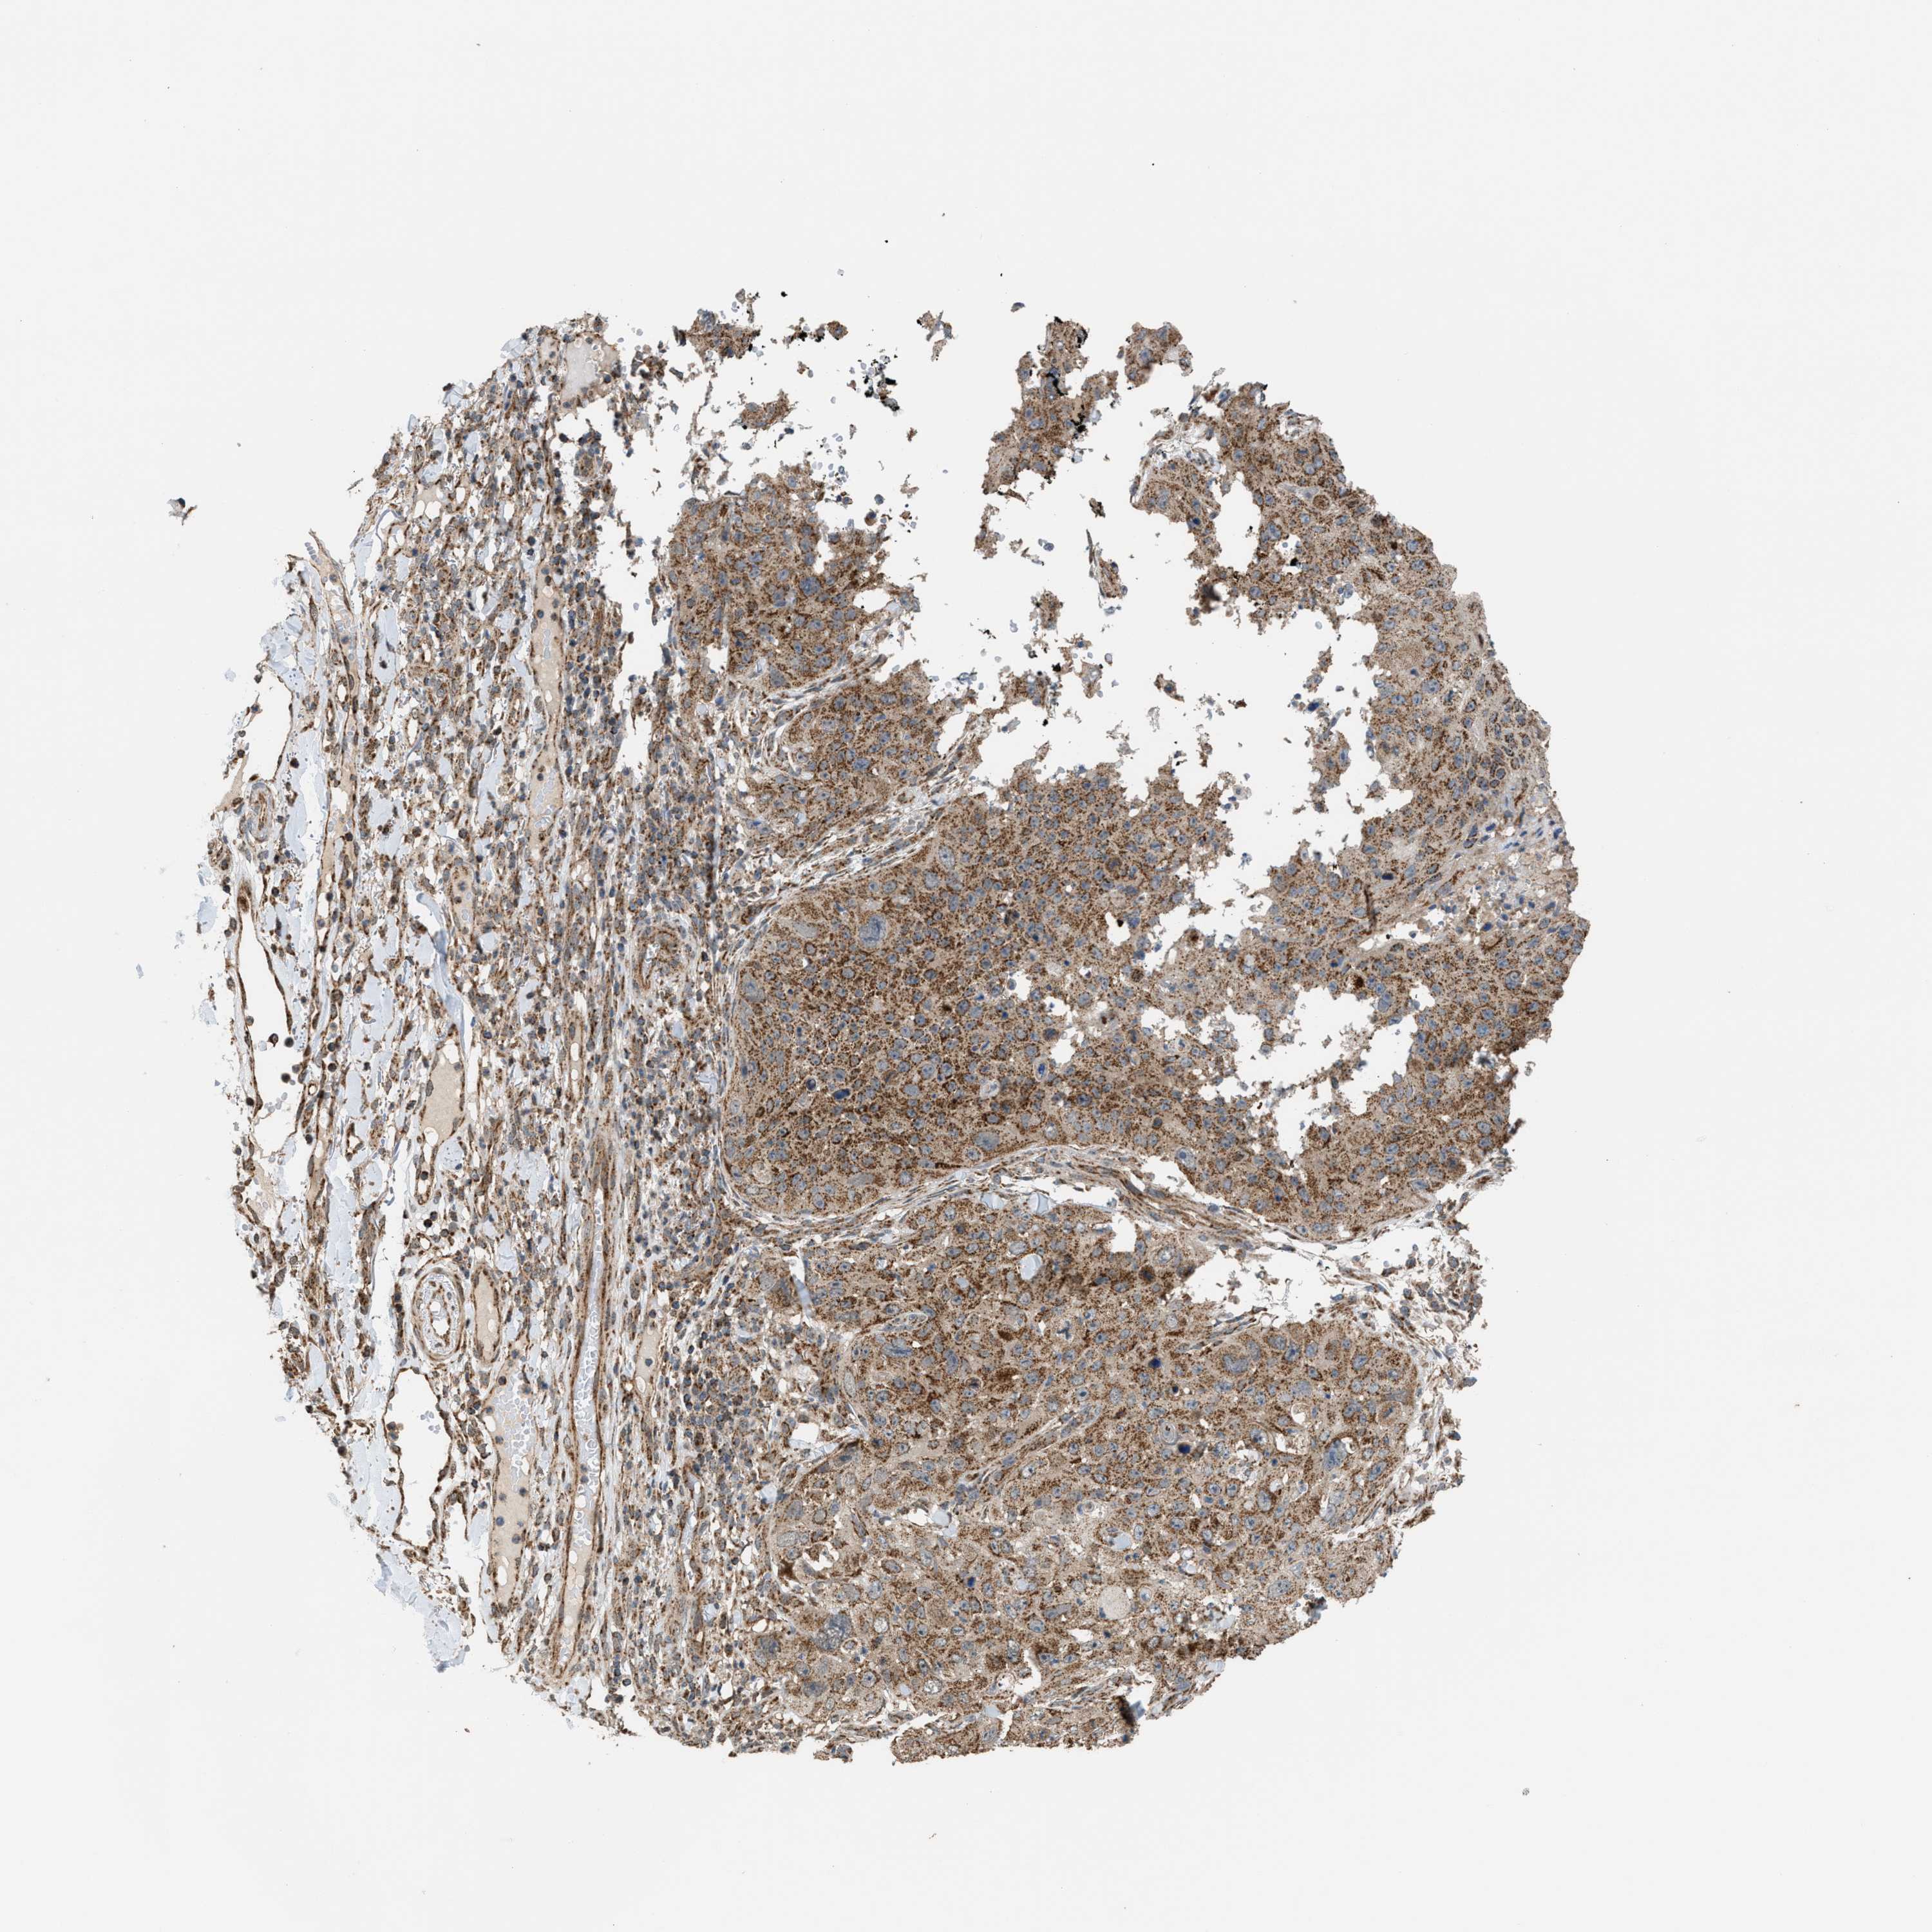

SKIN CANCER - Protein expressioni

A mouse-over function shows sample information and annotation data. Click on an image to view it in a full screen mode. Samples can be filtered based on level of antibody staining by selecting one or several of the following categories: high, medium, low and not detected. The assay and annotation is described here.

Each image is clickable and will lead to virtual microscopy that enables deeper exploration of all samples and also displays staining intensity scores, fraction scores and subcellular localization as well as patient and tissue information for each sample.

Antibody HPA021641

Staining

High

Intensity

Strong

Quantity

>75%

Location

Nuclear

Squamous cell carcinoma, NOS